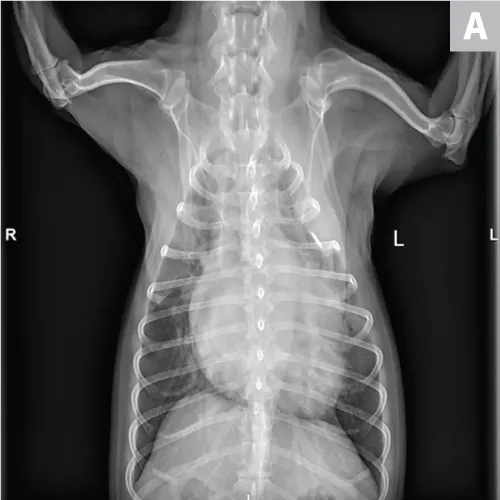

Cardiogenic edema is caused by increased hydrostatic pressure and is readily diagnosed by thoracic radiographic documentation of left-sided cardiomegaly, pulmonary venous congestion, and a patchy interstitial or alveolar pattern (frequently perihilar). Echocardiographic evaluation may support diagnosis.23 Natriuretic peptides may provide additional insight in differentiation between congestive heart failure and other causes of respiratory distress (Figure 4). Plasma B-type natriuretic peptide has been shown to have discriminatory value in dogs; however, some degree of overlap exists between groups.24

FIGURE 4A

Congestive heart failure. Note the left-sided cardiomegaly, pulmonary venous congestion, and interstitial pulmonary pattern. Edema is not exclusively perihilar.